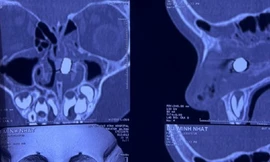

TPO - Nhập viện trong tình trạng đau đớn, mũi liên tục bị rỉ máu, cậu bé 5 tuổi được bác sĩ xác định bị viên pin điện tử phá hủy sụn vách ngăn. Dù đã được cấp cứu, xử lý tình trạng hoại tử nhưng bệnh nhi phải đối mặt với di chứng thủng vách ngăn suốt đời.